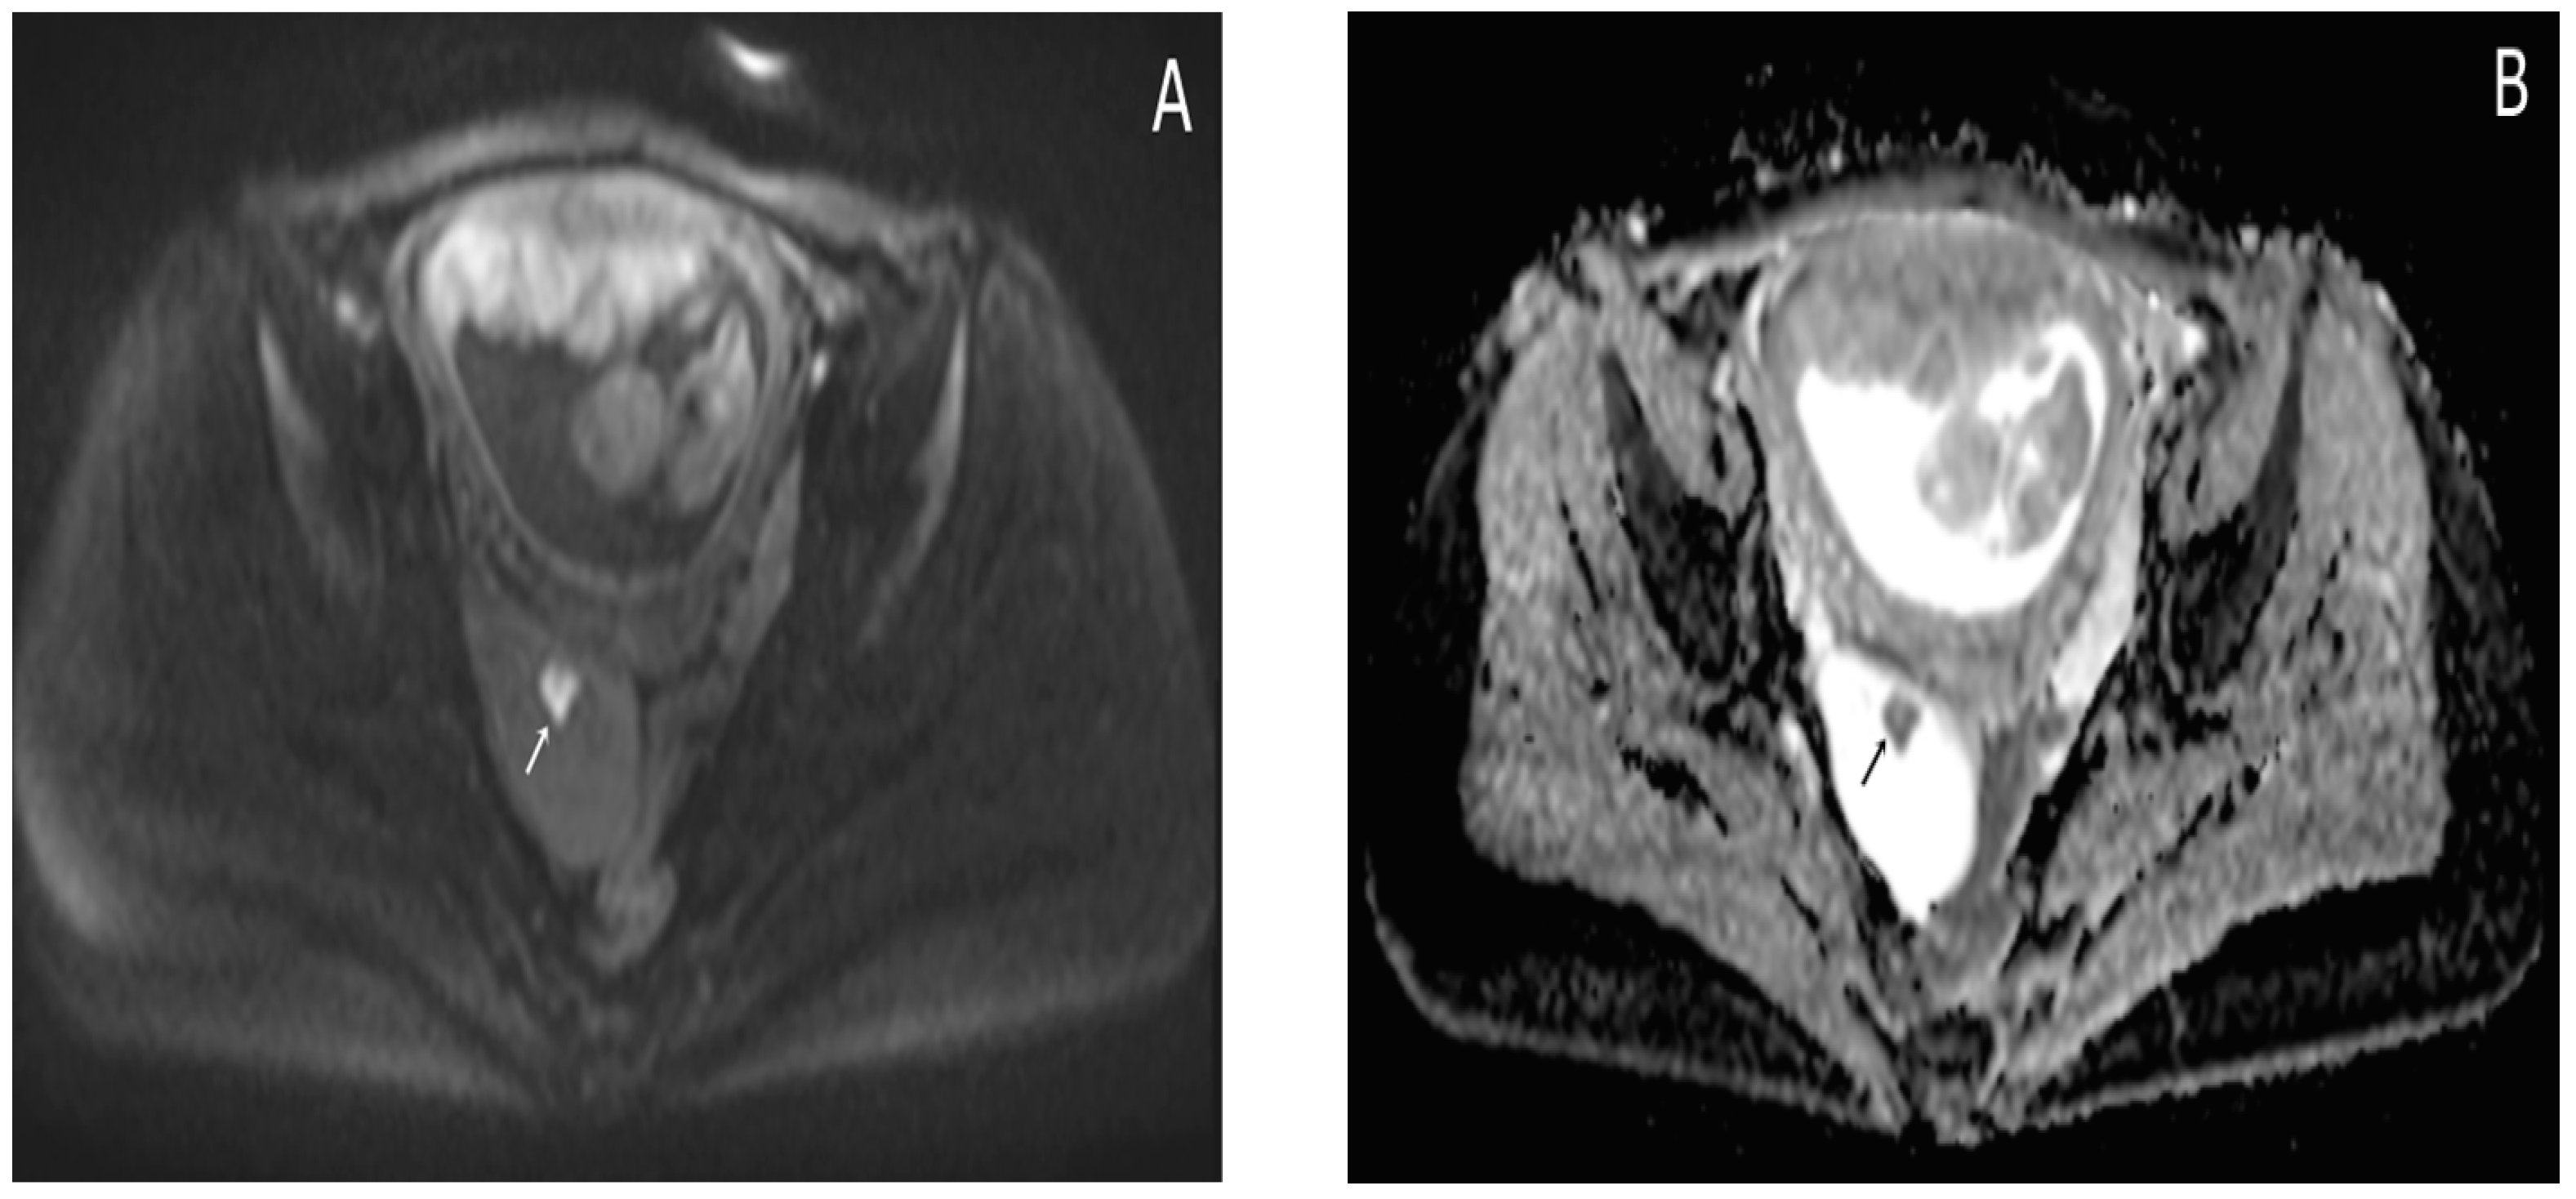

Almost a week later she performed a native MRI which highlighted: uterus with cranio-caudal dimensions of approximately 17 cm, no suspicious lesions at the level of the fetal content are visualized on the sequences performed; the left ovary measures approximately 37 mm in the anteroposterior plane; a space-replacing cystic process (ORADS4), located at the level of the right ovary, extended over an area of up to 56/45/60 mm (ap/ll/cc), reveals filiform septation of up to 2 mm in the right anterolateral quadrant, inhomogeneous solid inclusions with a thickness of up to 9 mm, approximately 3 papillary projections, intralesional hemorrhagic stigmata and a wall with a thickness of up to 3 mm; no space-replacing processes evident on MRI at the level of the rectal wall; no bone lesions with an oncological meaning evident in the examined MRI field; infracentimetric lymph nodes in the short axis located at the level of the internal and external iliac stations bilaterally (Figure 4, Figure 5 and Figure 6).

Figure 4. Sagittal TSE-T2WI images (A) and coronal TSE-T2WI (B) images show a thin smooth-walled unilocular cystic mass located behind the uterus, measuring (56 × 45 × 60 mm) with irregular soft tissue components (short arrow), papillary projections protruding into the lumen (long arrow) and incomplete internal septations (black arrow); there is a small amount of fluid around the lesion (dotted arrow).

Figure 5. Axial T1WI-TSE image (A) and axial T2WI-TSE image (B) show a unilocular right ovarian cystic mass. The signal intensity of the cystic component demonstrates intermediate signal on T1WI and high signal on T2WI. The intracystic papillary projection appears hyperintense on T1WI and hypointense on T2WI (arrows).

Figure 6. Axial DWI b800 s/mm2 image. (A) hyperintensity of the papillary projection of the endometrioma (arrow); apparent diffusion coefficient (ADC) map axial image. (B) low signal intensity of the papillary projection (arrow); these findings show restricted diffusion of the papillary projection; the cystic component shows no restricted diffusion.